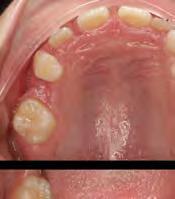

–MARPE, una alternativa a la disyunción en el paciente adulto, por el Dr. Enrique Solano y cols. [88]